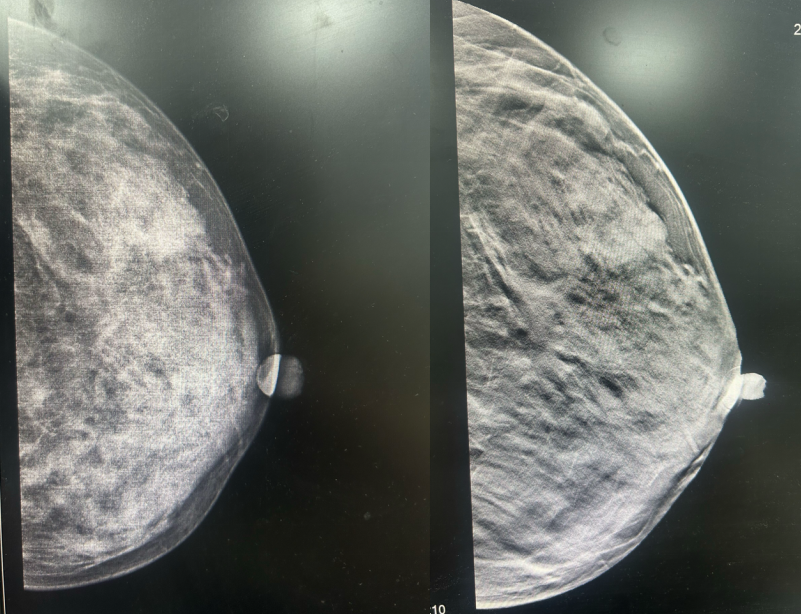

·乳腺MR

图2.2023年6月28日乳腺MR结果

1、左乳外下象限肿块,考虑恶性。(BI-RADS 5)

2、左侧乳头凹陷并强化,左乳下份皮肤结节样强化,请结合临床及其他检查。

3、右乳外份条带样异常信号,硬化性腺病与其他待鉴别,必要时活检。(BI-RADS 4A)

4、双乳多发点结状强化灶。(BI-RADS 3)

·乳腺DR

图3.2023年6月27日乳腺DR结果

1、左乳外下象限前中带肿块,恶性可能。(BI-RADS 4C)

2、右乳外上象限中后带局限性非对称致密,建议进一步检查。(BI-RADS 0)